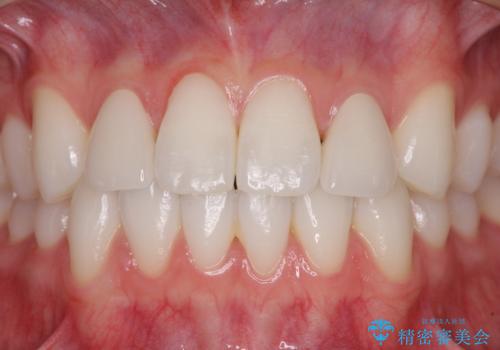

ホワイトニングを併用し、治療前と比べて自然でとても明るい口元となりました。